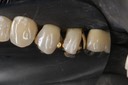

Ted Kanamori #18-19 caries removal